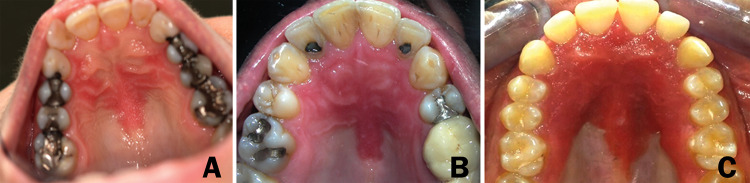

We have retrieved a total of 13 patients (six females and seven males; aged 11 to 56 years at diagnosis) who fulfilled the above criteria. The patient characteristics and their clinical features, including intra- and extra-oral manifestations, are presented in Table 1 and in Figs. 1, 2 and 3. All patients presented with a remarkable, well-demarcated symmetrical fiery-red erythema on the palatal mucosa, especially in the pre-maxilla (area of the rugae) (Fig. 1). Focal fiery-red hyperplastic gingivae in the upper jaw were recorded in 3 patients (#7, #8 and #13; Fig. 2a). Fissured tongue was noticed in 6 cases (#2, #3, #4, #5, #8 and #13; Fig. 2b), and geographic tongue in 4 patients (#2, #3, #5 and #11; Fig. 2b). Involvement of the lip commissure, presenting as angular cheilitis, was seen in patient #8.

Fig. 2.

Oral (non-palatal) lesions/conditions. a Gingival involvement in patient #13. b Tongue involvement: geographic and fissured tongue in patient #3

None of our patients reported a familial history of hereditary mucoepithelial dysplasia (HMD). Eight patients presented dermal conditions, such as psoriasis (#3, #6, #10, and #12; Fig. 3a), atopic dermatitis (#8 and #9), alopecia (#9; Fig. 3b) and ichthyosis vulgaris (#13). The patients with psoriasis were reassessed by an experienced dermatologist (A.B.) who had confirmed this diagnosis. Five patients were otherwise healthy without any diagnosed medical condition (#1, #2, #4, #7 and #11).

Two patients used removable partial dentures (removed at night; patients #5 and #10) and one had an orthodontic retainer (only at night; #8). In contrast to denture stomatitis, no correlation was noticed between the location and shape of the appliances and the oral lesions.